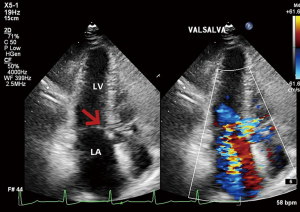

Twelve-lead electrocardiogram showed ST-T segment depression and signs of left ventricular hypertrophy. Transthoracic echocardiography (TTE) showed asymmetric septal hypertrophy with a maximal wall thickness of 16 mm at the LVOT level. Transesophageal echocardiography (TEE) revealed significant SAM of the anterior mitral leaflet (Figure 1, Video 1), causing dynamic LVOT obstruction (Figures 2,3) and severe MR (Figure 2, Video 2). On Valsalva maneuver, the LVOT pressure gradient reached 233 mmHg. Her left atrium was dilated and pulmonary artery systolic pressure was elevated. Reversed systolic wave was observed in the pulmonary vein flow (Figure 4). No abnormal muscle bundles were observed on imaging, including TEE and TTE.

To relieve MR and dynamic obstruction, the team opted for TEER with the MitraClip™ system. Pre-procedural TEE confirmed moderate to severe MR, a mitral valve effective regurgitant orifice area of 0.31 cm2, and a regurgitant volume of 78 mL. The mitral valve area was 3.1 cm2 (planimetrically measured in multiple views), with leaflet lengths of 24 mm (anterior) and 11 mm (posterior). The diastolic mean trans-mitral gradient was 1 mmHg. The regurgitant jet originated from the A2–P2 segment with reversed pulmonary vein flow.